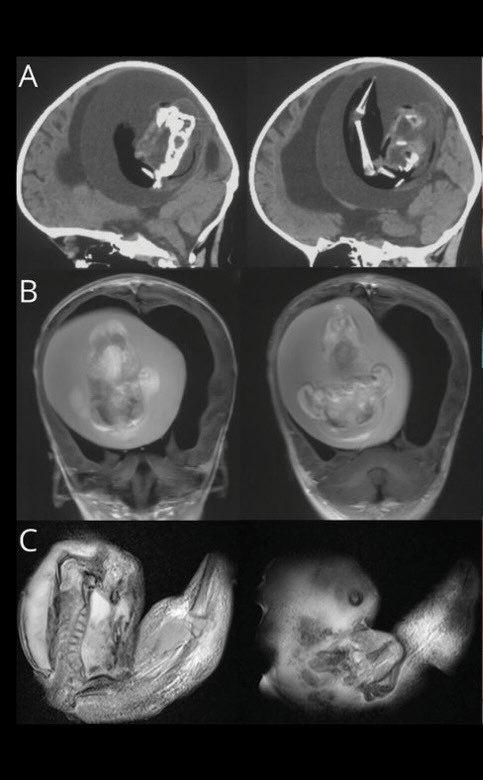

一岁的女孩来自上海显示一些指示性的问题,比如扩大头和运动技能不足。CT扫描显示,她的大脑被压缩,有过多的液体引起的心室,增长被发现是孩子的未出生的双胞胎。fetus-in-fetu成立了上肢和附件类似手指,虽然它的其他形式是严重不发达。

虽然这种现象最可能听起来奇怪,它被称为“fetus-in-fetu”,是极其罕见的。它发生在双胎妊娠的早期胚泡的时候,一群细胞分裂,无法正常分离,导致一个胚胎被对方包围。

包膜胚胎未能发展但仍然“活着”由于其他双胞胎的血液供应。的结合部分胚胎发育成胎儿前脑的主机和信封其他胚胎神经板折叠。